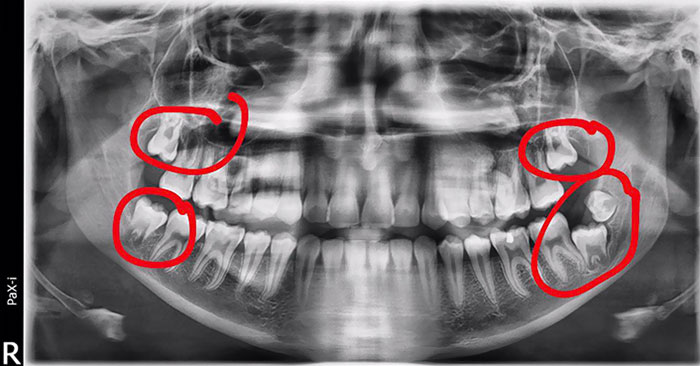

I Have A Rare Disorder Called Cleidocranial Dysotosis. Got My First Dental X-Ray Today And I Have A Lot Of Extra Teeth

I Took An X-Ray Today And They Told Me That My Wisdom Teeth Are Pretty Strange

I Have 5 Wisdom Teeth

I Went To The Dentist For Tooth Pain, I Got My X-Rays Taken And The Dental Assistant Said My Wisdom Teeth Were "Like Something Out Of A Textbook"